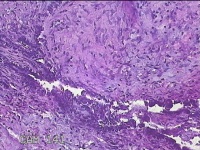

右侧卵巢囊肿

性别

女

年龄

36岁

临床诊断

一般病史

发现双侧附件囊肿1年。

标本名称

大体所见

灰白暗红色囊壁样组织2.5x2x0.3cm一块,表面光滑,部分已切开,囊内容物已流失,囊壁厚0.2cm。

考虑:子宫内膜异位囊肿。